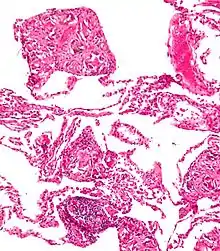

استجابة الأجسام الغريبة للتالك (السحار التلكي) نتيجة استخدام العقاقير عبر الوريد. صبغة الهيماتوكسيلين والأيوزين.

يؤدي وجود الطعم المغروس في الجسم إلى تغيير مدى استجابة الالتئام، وهذا ما يسمى بـتفاعل الجسم الغريب (FBR). يتضمن تفاعل الجسم الغريب : امتصاص البروتين والبلاعم والخلايا العملاقة للأجسام الغريبة متعددة النواة (انصهار البلعم) والأرومة الليفية و تولد الأوعية.